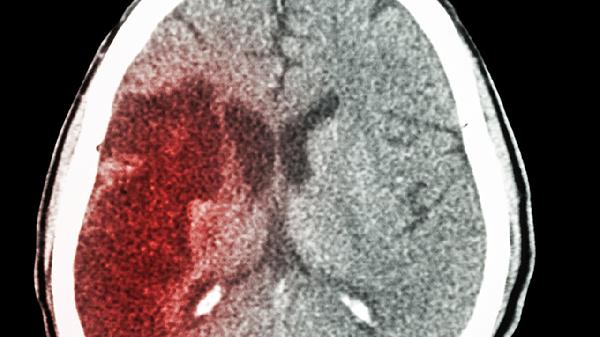

对于轻度脑动脉硬化或颈椎病导致的脑供血不足,健脑补肾丸可能改善头晕目眩、头重脚轻等症状。其丹参、川芎等活血成分有助于促进微循环。但急性脑血管病不属于该药适应证,出现剧烈头痛、呕吐时须立即就医。可联合血塞通片增强效果。